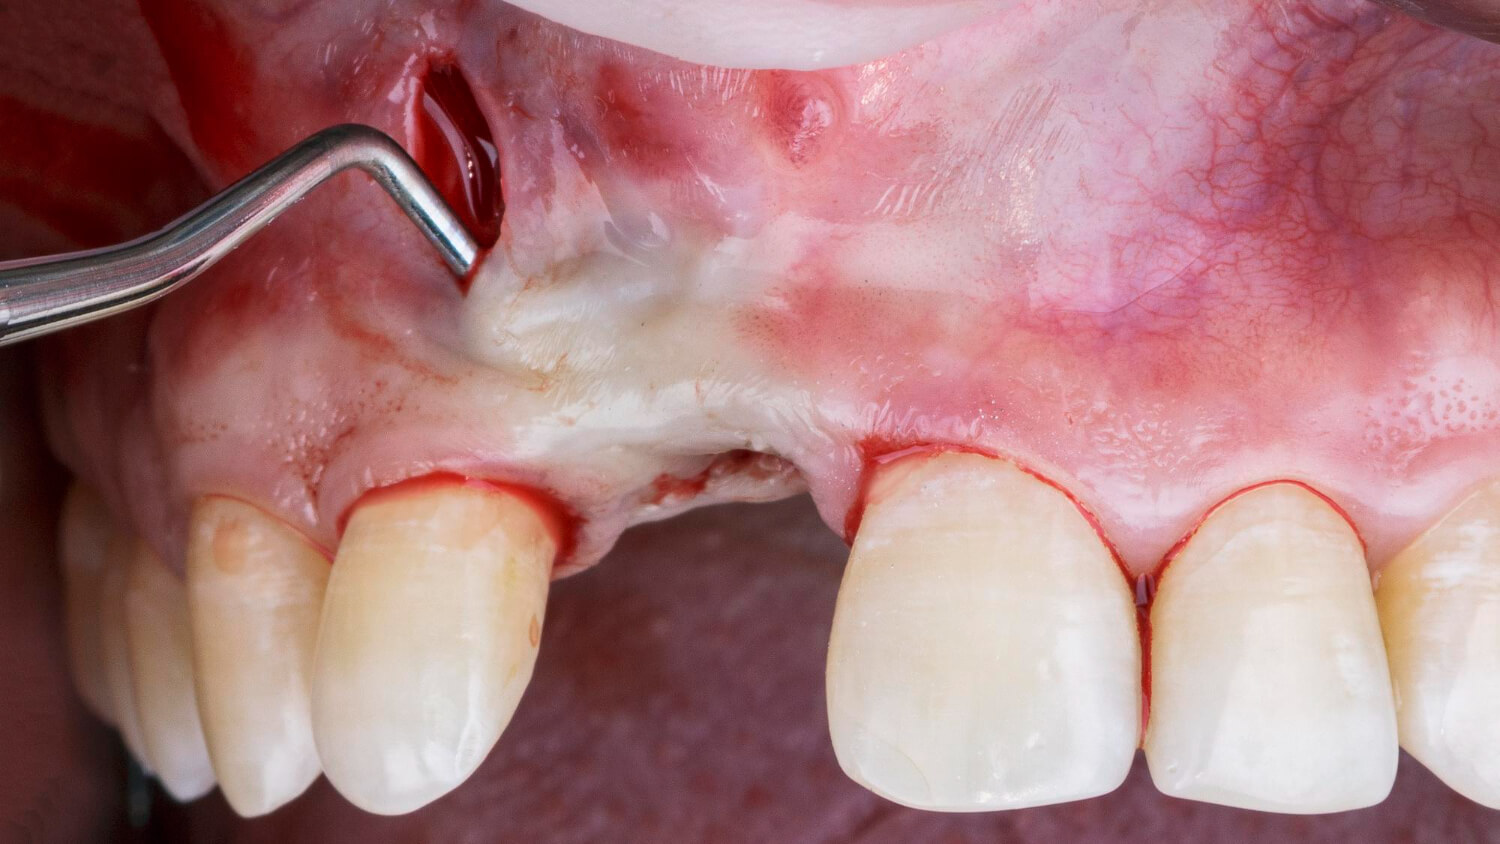

Nyílt (külső) sinus lift

A nyílt sinus lift műtét egy nagyobb volumenű csontpótló beavatkozás, amely bonyolultabb, ha a csontmagasság jelentősen lecsökkent (4 mm-nél kevesebb).

Menete részletesen:

- Az íny oldalirányú megnyitásával egy kis csontablakot készítünk a csont íny felőli felületén.

- A nyálkahártya és a csont közé bőséges csontpótló anyagot juttatunk, így jelentős csontvastagság hozható létre.

- Az ínyt visszazárjuk és varratokat helyezünk fel.

Nyílt sinus lift esetén gyakran külön kezeléssel, csak hónapokkal később történik az implantáció, amikor már megfelelő mennyiségű új csont képződött. Bár komplexebb beavatkozás, a hosszú távú eredmények kiválóak.